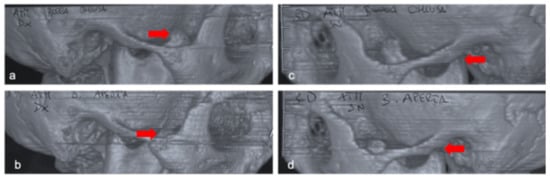

Mandibular Coronoid Process Hypertrophy: Diagnosis and 20-Year Follow-Up with CBCT, MRI and EMG Evaluations

2. Clinical Case